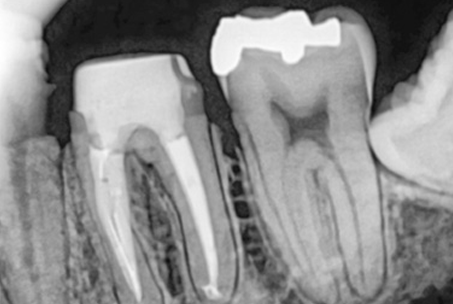

위 사진들은 현직 치과의사들이

저희 웃는얼굴 치과에서 치료 받은 실제 사례들입니다.

비 전문가 눈에는 그냥 흔한 엑스레이 사진일 뿐이겠지만

치과의사들이라면 알아챕니다.

저 치료가 얼마나 난이도 있는 치료였는지,

얼마나 정성이 들어갔는지를 말이지요.